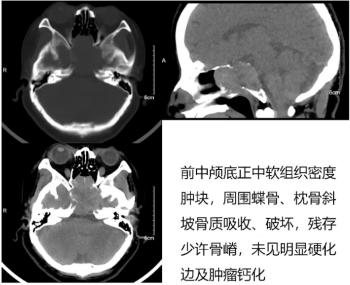

1) 鞍区CT平扫:病灶位于前正中颅底中线区,呈软组织密度,周围蝶骨及枕骨斜坡骨质吸收破坏,残存少许骨嵴,未见明显硬化边及肿瘤钙化。